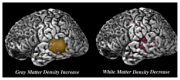

Children prenatally exposed to alcohol can suffer from serious cognitive deficits and behavioral problems as well as from alcohol-related changes in brain structure. Neuropsychological studies have identified deficits in learning and memory as well as in executive functioning both in children with fetal alcohol syndrome and in children with less severe impairments. Both groups of children also exhibit problem behaviors, such as alcohol and drug use, hyperactivity, impulsivity, and poor socialization and communication skills. Brain imaging studies have identified structural changes in various brain regions of these children--including the basal ganglia, corpus callosum, cerebellum, and hippocampus--that may account for the cognitive deficits. Functional brain imaging studies also have detected changes in alcohol-exposed children indicative of deficits in information processing and memory tasks.